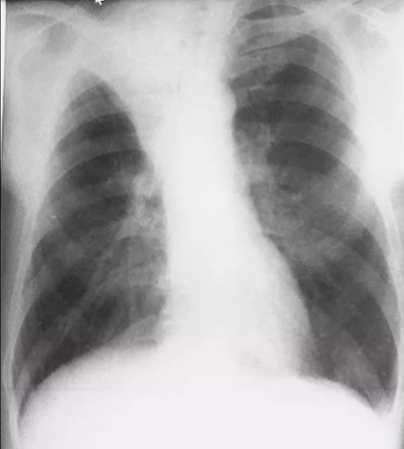

Rx toracică, incidență P-A

DESCRIERE:

pe tot teritoriul pulmonar, bilateral → opacități nodulare multiple de dimensiuni variabile, intensitate medie-mare, omogene, cu contur net

distribuție anarhică

blocuri adenopatice la niv. hilurilor pulmonare

DX: MTS pulmonare hematogene

DD:

hidatidoză - dimensiuni mai mari

bronhopneumonie - contur neregulat, neomogene, distribuție bazală